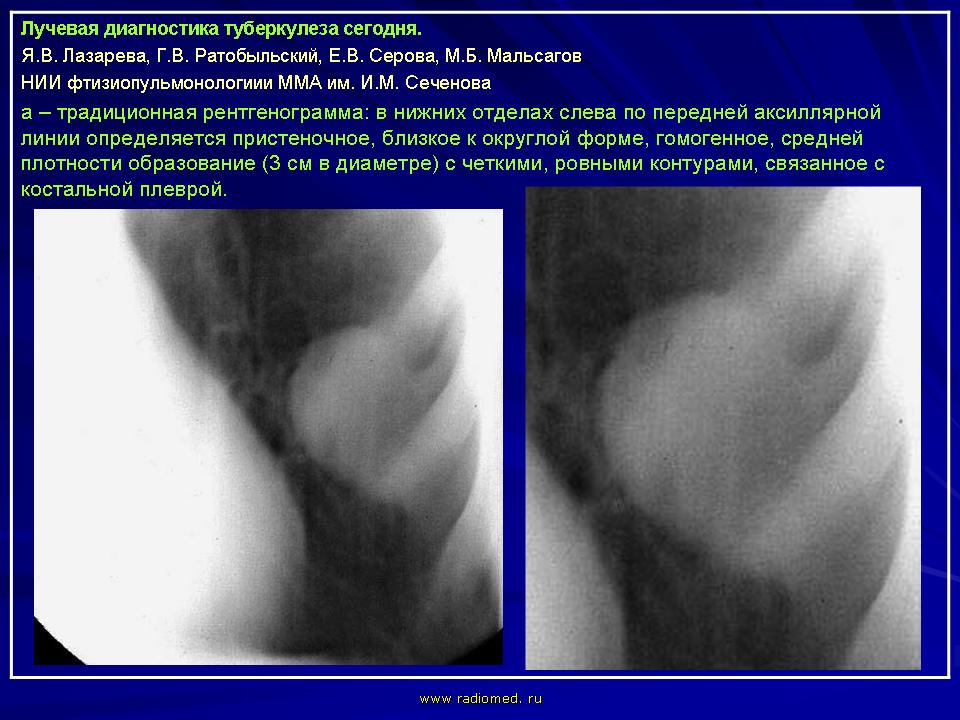

Лучевая диагностика туберкулеза сегодня

Я.В. Лазарева, Г.В. Ратобыльский, Е.В. Серова, М.Б. Мальсагов

НИИ фтизиопульмонологиии ММА им. И.М. Сеченова